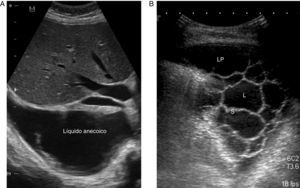

La ET es una técnica básica en el manejo del DP, especialmente del DPP, que los neumólogos deberían dominar. Es más sensible que la Rx para detectar un DP pequeño, establece la ecogenicidad del LP, localiza con precisión el líquido loculado, estima el volumen y la profundidad del DP, diferencia entre LP y consolidación subyacente o atelectasia, mejora el rendimiento de la toracocentesis y disminuye el riesgo de complicaciones en comparación con el uso conjunto de exploración física y Rx24. La presencia de septos en la ecografía sugiere un DPPC (fig. 2), y la hiperecogenicidad se asocia con pus en la cavidad pleural.